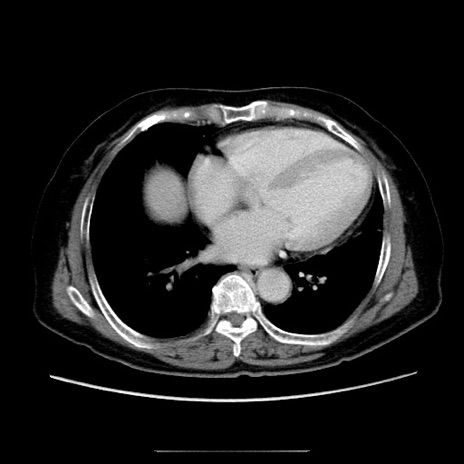

症例5(横断像)

【症例】70歳代女性

【主訴】お腹が張る

【現病歴】1週間くらい前から腹部膨満の自覚あり。昨日夜から増悪したため、本日救急外来受診。

【身体所見】意識清明、BT 36.5℃、BP 165/106mmHg、HR 80bpm、SpO2 98%、腹部:膨満、軟、自発痛・圧痛なし、触診にて不快感あり、腸蠕動音:減弱

【データ】WBC 12600、CRP 1.04